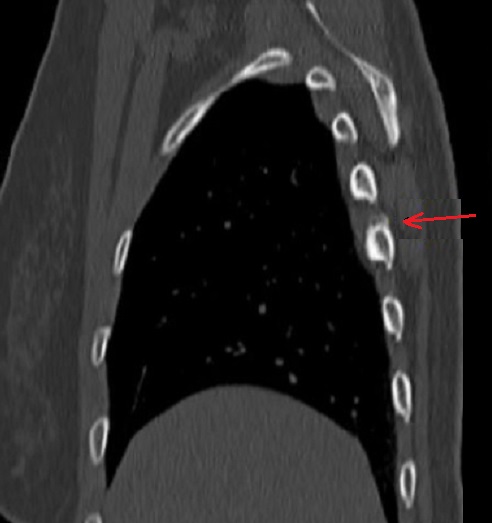

Aspect radiologique TDM de

nodule calcification parietale (flèche rouge )

d'une myosite ossifiance chronique de muscle

intercostale posterieure droit . Image radiologique

TDM en coupe axiale |

Même cas en coupe sagitale .

La depôt calcique être en vue tres net au bord

superieure , arch posterieure du côte 4th

droit du thorax . Myosite ossifiance chronique .